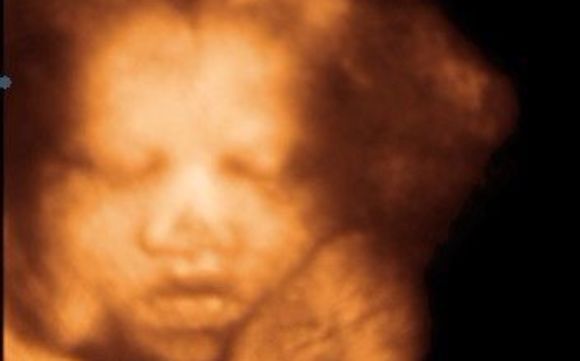

3d Ultrasound Jacksonville Fl

Baby Bloom 4d Ultrasound Studio 3d 4d Hd Early Gender Reveal

Top 10 Local Favorite 3d Ultrasound In Jacksonville Fl Last